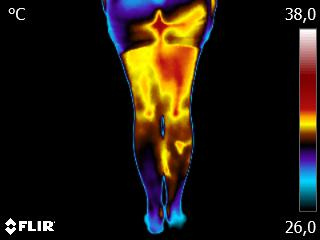

Como no caso do termograma abaixo de abaixo de uma paciente, do sexo feminino, 51 anos, sem comorbidades e que apresentou dor em posterior de coxa após atividade física. Foi realizado um Exame Termofuncional e detectado alterações térmicas condizentes com o relato de dor.

Através dos conhecimentos e estudos da Técnica Termofuncional, foi verificado que estas alterações estavam associadas ao comprometimento da muscular da cadeia posterior, permitindo determinar a causa da dor.

Isso somente foi possível pelo estudo e conhecimento da Técnica Termofuncional, pois ela possui um procedimento reprodutível e escalável.